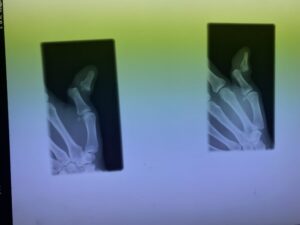

第16回整骨研究会「賜恩」研修会開催

さわやか千葉県民プラザ(指骨骨折)

第18回整骨研究会「賜恩」研修会開催

第20回整骨研究会「賜恩」研修会開催

さわやか千葉県民プラザ(指の脱臼)

第22回整骨研究会「賜恩」研修会開催

春日部市市民活動センター(指の脱臼)